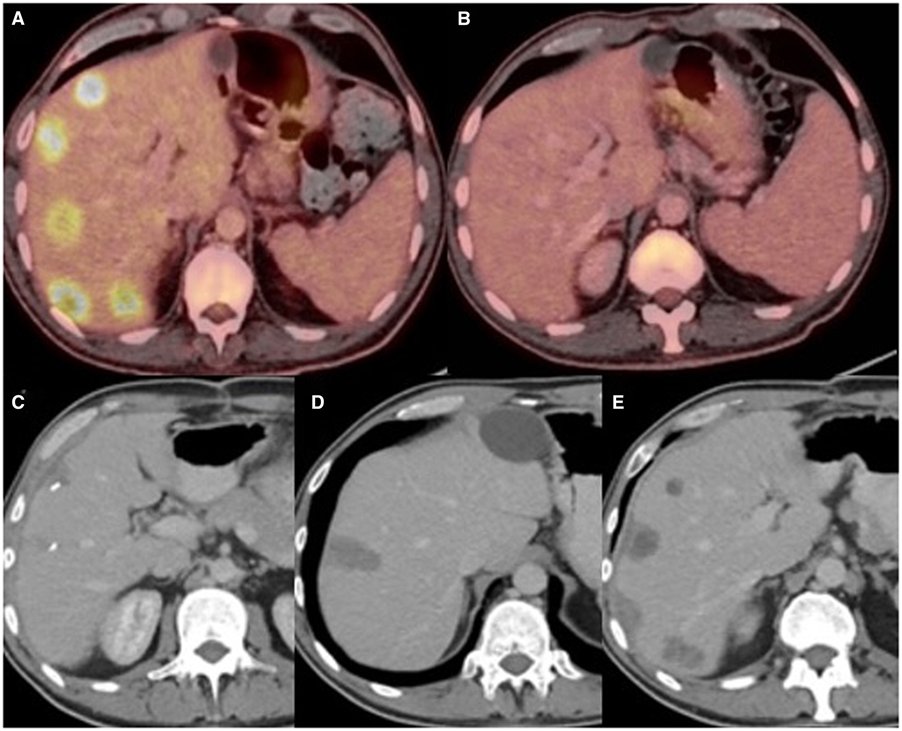

🚨EASL CPG on the management of HCC in @JHepatology Major update! ✅ LI-RADS endorsed ✅ Refined treatment algo ✅ More evidence supporting locoregional treatments ✅ Up-to-date discussions 👉bit.ly/3VKZmcy